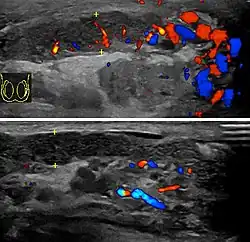

Before the advent of sophisticated medical imaging techniques, surgical exploration was the standard of care. Today, Doppler ultrasound is a common test: it can demonstrate areas of blood flow and can distinguish clearly between epididymitis and torsion. However, as torsion and other sources of testicular pain can often be determined by palpation alone, some studies have suggested that the only real benefit of an ultrasound is to assure the person that they do not have testicular cancer.[12]: p.237 Nuclear testicular blood flow testing may be used.[13]